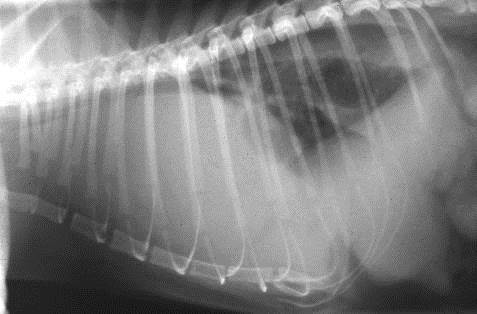

Discuss this radiograph?

Subcutaneous emphysema

Can get useful info about what has happened about changes going on within the thorax, VD of cat

Can see increase opacity and cannot see cardiac silhouette – but can see air and lucencies in subcut tissues

SUBCUTAENOUS EMPHYSEMA – suggests some kind of trauma and some leaking from airways at some point